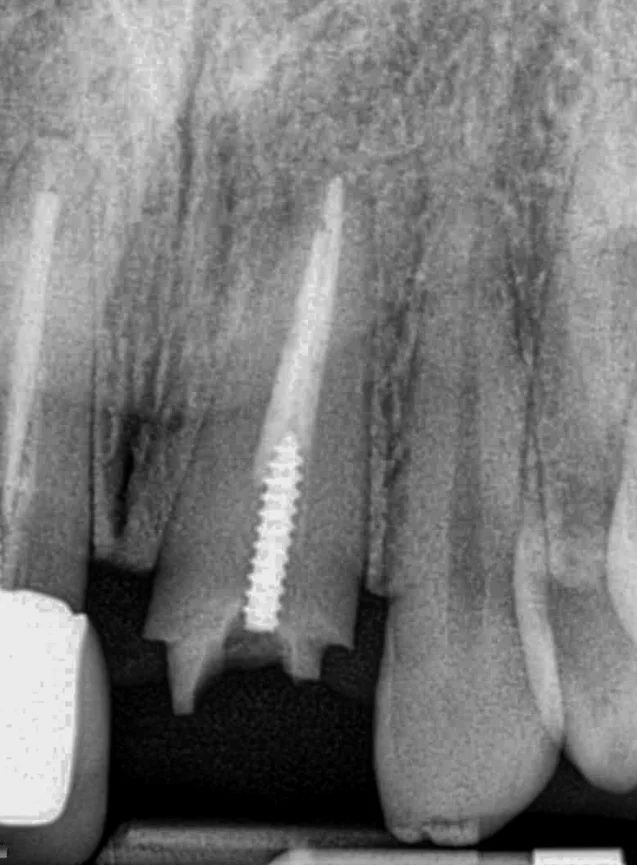

Removed post and surgically repositioned for 2 mm ferrule

Crowns delivered after 12 weeks of the surgical repositioning. Happy patient.

Bicon implant placement and restorations

#30 Bicon implant placement and restoration.

#12 extraction and placement of Bicon implant